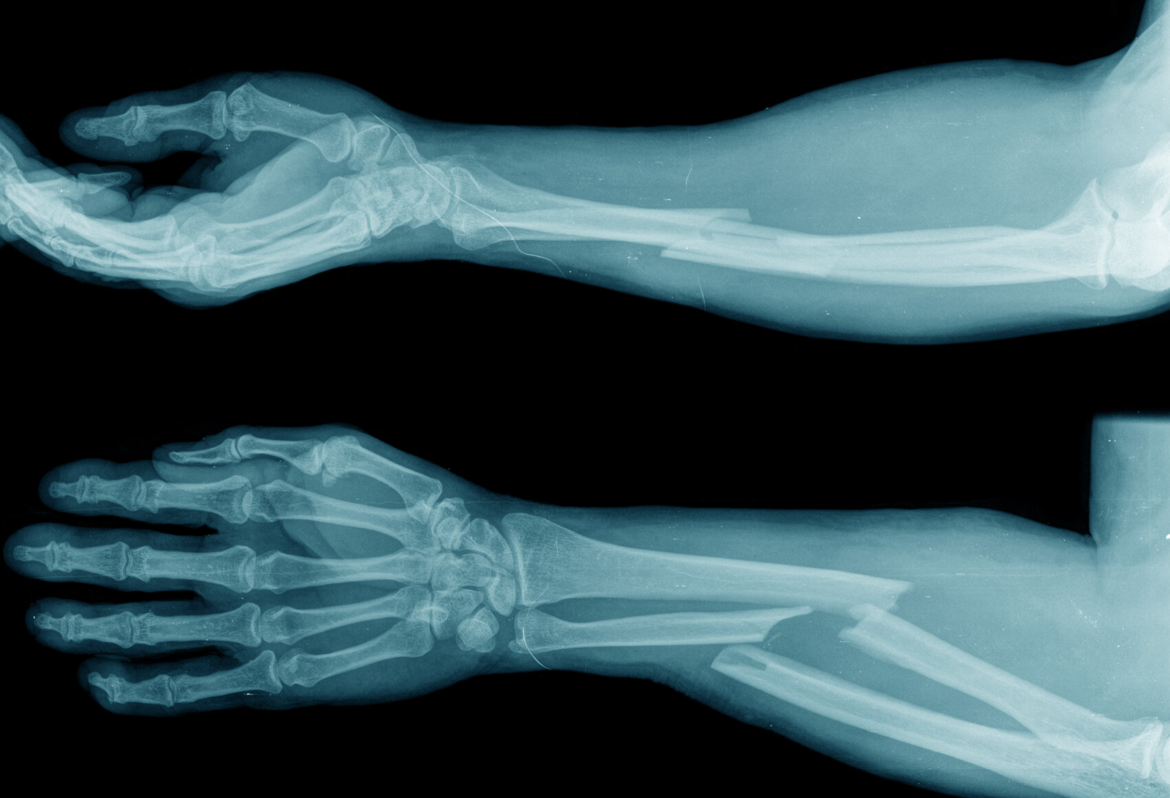

Fractures, or broken bones, are common injuries that can occur due to accidents, falls, or high-impact activities. While many fractures heal naturally with proper immobilization and rest, some require surgical intervention to restore normal function and ensure optimal recovery. Understanding when a fracture needs surgery is essential for timely treatment and the best outcomes.

Open Fractures

Also called compound fractures, these occur when the bone pierces through the skin, increasing the risk of infection. Surgery is often needed to clean the wound, align the bone, and stabilize it with internal or external fixation.

Severely Displaced Fractures

When the broken bone fragments are far apart or misaligned, surgery is required to reposition them. Techniques like using plates, screws, or rods help ensure proper alignment and healing.